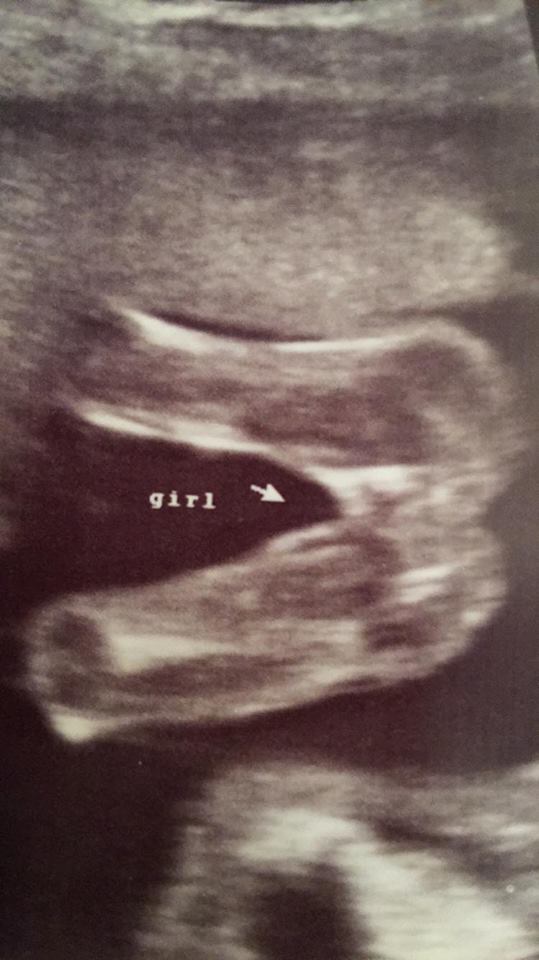

My name is Franchesca; I am very excited for this pregnancy! I recently had my 20 week ultrasound (though I was 19 weeks and 3 days), and the ultrasound technician said she believes it is a girl. I was ecstatic to hear so, because this is what I was hoping for.

Does this look like a girl to you all?